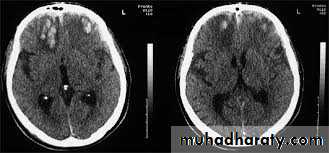

• Extracerebral haematomas show a high density for about 1–2 weeks following the injury, but after 3–4 weeks the density decreases to become lower than that of the brain. In the intervening period, haematomas pass through a phase of being isodense with the brain

• Causes Midline or ventricular displacement.

• Extradural haematoma is seen as a lens-shaped, smoothly demarcated, high-density area situated over the surface of the hemisphere associated with a skull fracture

• Subdural haematoma conforms to the shape of the underlying brain (crescentic shape) and occurs most commonly over the convexity of the brain, but can also arise along the falx and tentorium

• Contusions are bruises of the brain which appear as areas of low attenuation and may be associated with high-density areas due to haemorrhage.

• Intracerebral haematomas are seen as areas of high density, which may be multifocal. There may be mass effect causing displacement of the ventricles and accompanying brain oedema.